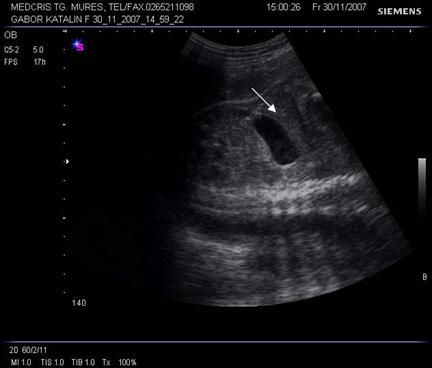

Fig. nr.176. Planul 0 de sectiune transversala ptr examinarea cordului, se incepe cu abdomenul , in care se remarca stomacul si aorta ( cu o sageata ) alaturi spre dreapta , vena cava inferioara ( cu doua sageti )